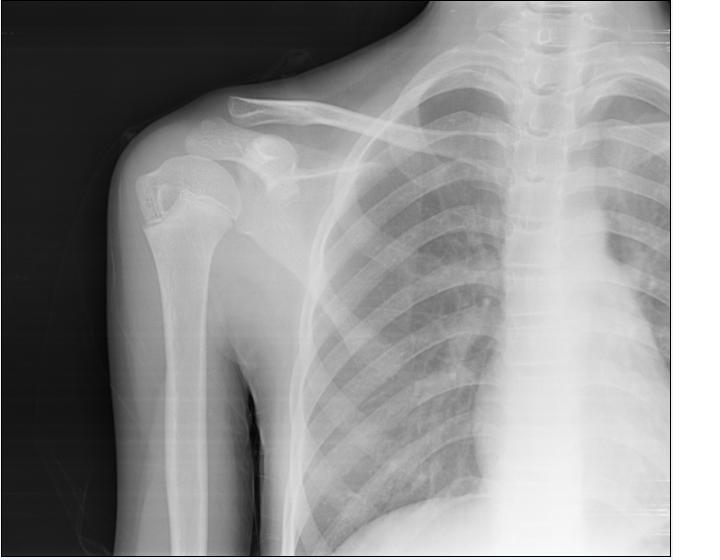

标题: CT22500:患者左肩痛一周,无其它不适,请会诊。 [打印本页]

标题: CT22500:患者左肩痛一周,无其它不适,请会诊。

是正常的骨骺吗?

未见明显异常